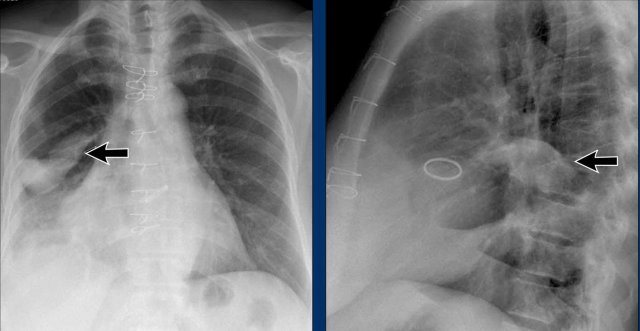

Left Atrial Enlargement

• Patient with a history of chronic mitral valve disease and valve replacement.

• Extreme dilation of the LA leads to bulging of both the right upper cardiac contour (black arrows) and posterior heart border on lateral view (blue arrow).

Right Ventricular Enlargement

First study the PA and lateral chest film and then continue reading.

Findings

• Chest radiographs show massive cardiomegaly, predominantly due to right ventricular dilation (yellow arrow on lateral view).

• Small aortic knob (blue arrow), with dilation of the pulmonary trunk and right lower pulmonary artery.

• Findings suggest a left-to-right shunt with secondary pulmonary hypertension.